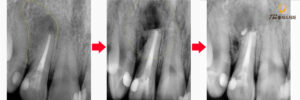

사진을 보시면

처음에 염증으로 가득 차있었던 부분이

깔끔하게 치유가 되며,

그 부위로는 조직으로

다시 채워짐을 기대해 볼 수 있습니다.